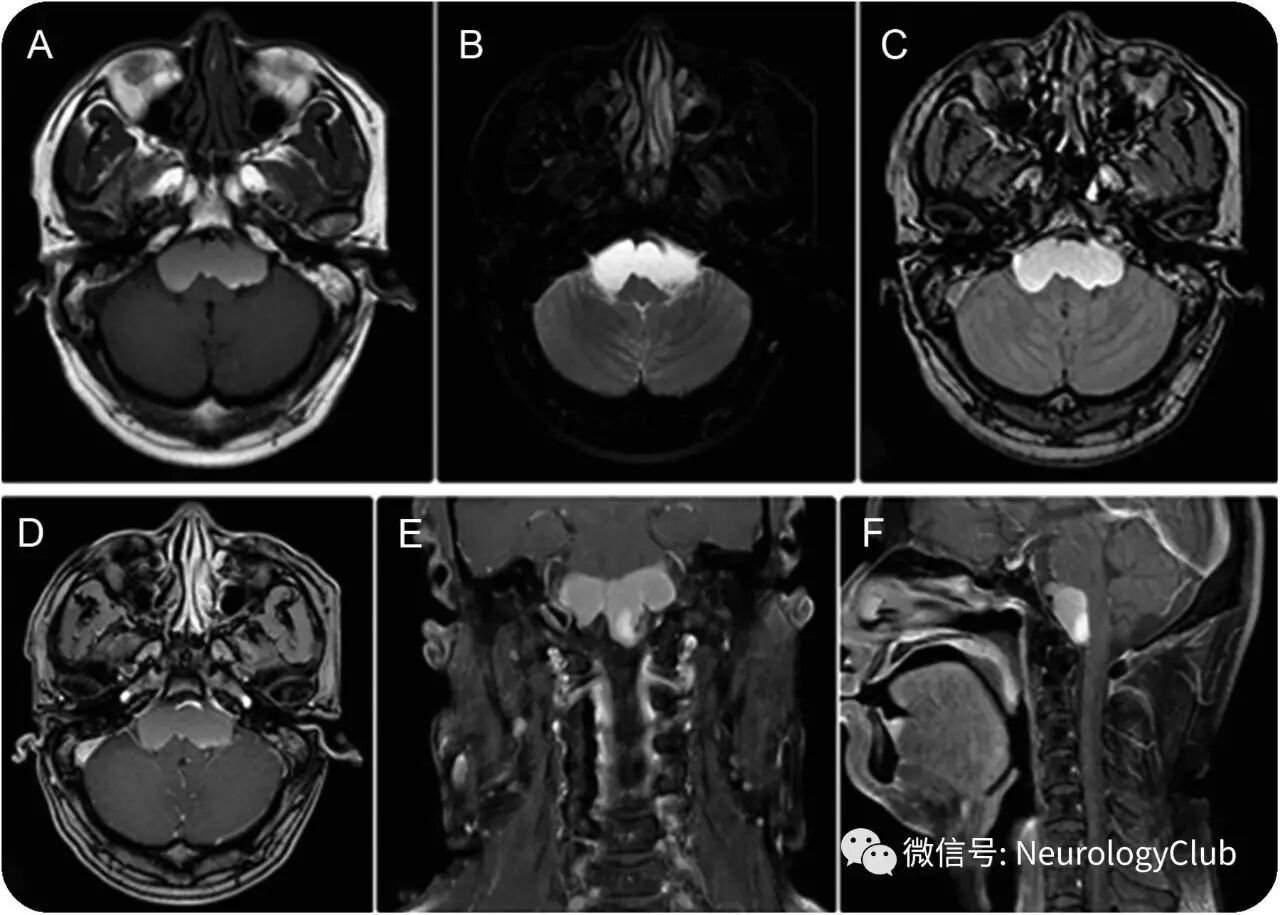

53岁男性,表现为间断性发热和进行性加重的头痛6月,伴左侧轻偏瘫(4级)以及新出现的步态不稳,余无殊。患者免疫功能正常,自行服用过扑热息痛-咖啡因-阿司匹林粉剂。2年前患者曾罹患化脓性脑膜炎,经腰穿确诊,当时脑脊液培养阴性,予以头孢曲松/万古霉素治疗2周。本次影像学检查证实脑桥前囊性肿块(图1)。

(图1:MRI可见脑桥前区域囊性肿块,T1WI[A],T2WI[B]和FLAIR[C]上呈均匀高信号;增强T1[D-F]可见病灶内一结节状强化)